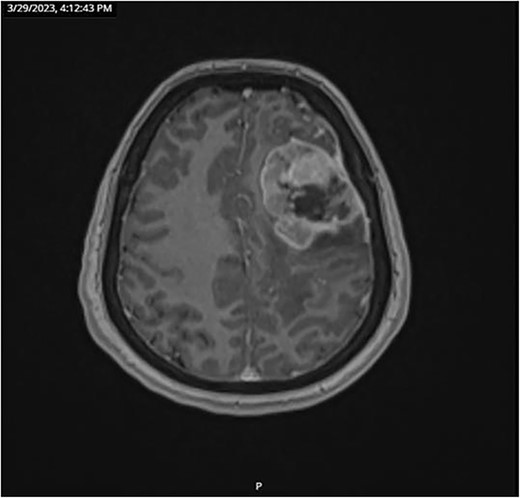

CT and PET scans revealed multiple positive lymph nodes, but metastatic lesions were not found in chest, abdominal organs, or bone (Fig. 2). Genetic and molecular tests revealed wild rat associated sarcoma, wild BRAF, proficient MMR, and negative HER-2. Tumor markers were positive. The patient started chemotherapy, which included CAPOX, cetuximab, and FOLFOX. PET scan was done for re-evaluation, and marked partial disease response was observed with currently no evidence of disease. After that, the patient started to experience reversible amnesia, bizarre behavior followed by right side upper limb weakness, hyperreflexia on the right side, positive Babinski sign on the left, and positive Hoffman sign bilaterally. Brain MRI was done, which revealed a left fronto-parietal extra-axial space-occupying lesion with vasogenic edema and midline shift (Fig. 3). Patient underwent brain lesion resection through left fronto-parietal craniotomy. The pathology revealed GBM (Fig. 4). IHC stain of neoplastic cells showed wild IDH and positive for GFAP, and 30% of the neoplastic cells showed positive for Ki67.